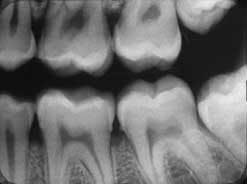

Posterior segments

Treat the posterior segments in a similar mesio-distal manner. The long axis of the film is placed in the Styrofoam holder (white side always toward the teeth) so that the film follows the occlusal plane of the arch. Again, placement of the film is of paramount importance in securing diagnostic quality X-rays. There is no excuse for improper placement of films in the arch by the clinician.

In each posterior segment, whether taking a periapical or bitewing of the bicuspids and molar views, the placement of the film is as follows:

• For the bicuspid view, the film is placed in the arch with the mesial of the film just barely touching the distal of the cuspid, if present. The bicuspid view will incorporate a full view of the first molar region as well. On the upper jaw, the angle of the X-ray head is preset at 30 to 35 degrees and the face of the tube parallel to the bicuspid-first molar region. Once the film is placed as described, aim the face of the tube like a rifle so the beam will be passing through the face of the teeth being X-rayed, without overlapping of the interproximal and avoiding cone cutting. Actually, you should determine that the open face of the tube is parallel to the bicuspid and first molar, and that the entire film is within the parameters of the open tube. With practice, this procedure should not take more than five to 10 seconds.

• Properly imaging the molar view in the arch depends on placing the film opposite the third molar area. This is done in a similar way as is used for the bicuspid view, except that the mesial of the film as it is placed in the mouth must be at the middle of the first molar. The patient is biting lightly on the Styrofoam holder. The angle of the X-ray head is set at 20 to 25 degrees in the upper arch. Once again, it's important to develop the ability to bring the face of the tube parallel to the second and third molars and aim the tube to send the beams perpendicular to the film to avoid overlapping. If the film is viewed as being entirely within the face of the tube, you will avoid cone cutting and interproximal distortion. This gives you a clear view of the second and third molar area, the distal half of the first molar and surrounding bone and soft tissue.